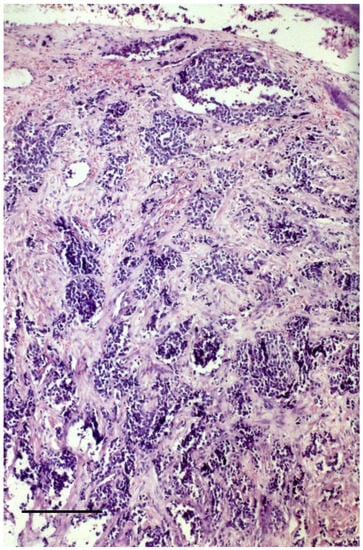

3.2. Histopathology of the Primary Tumor